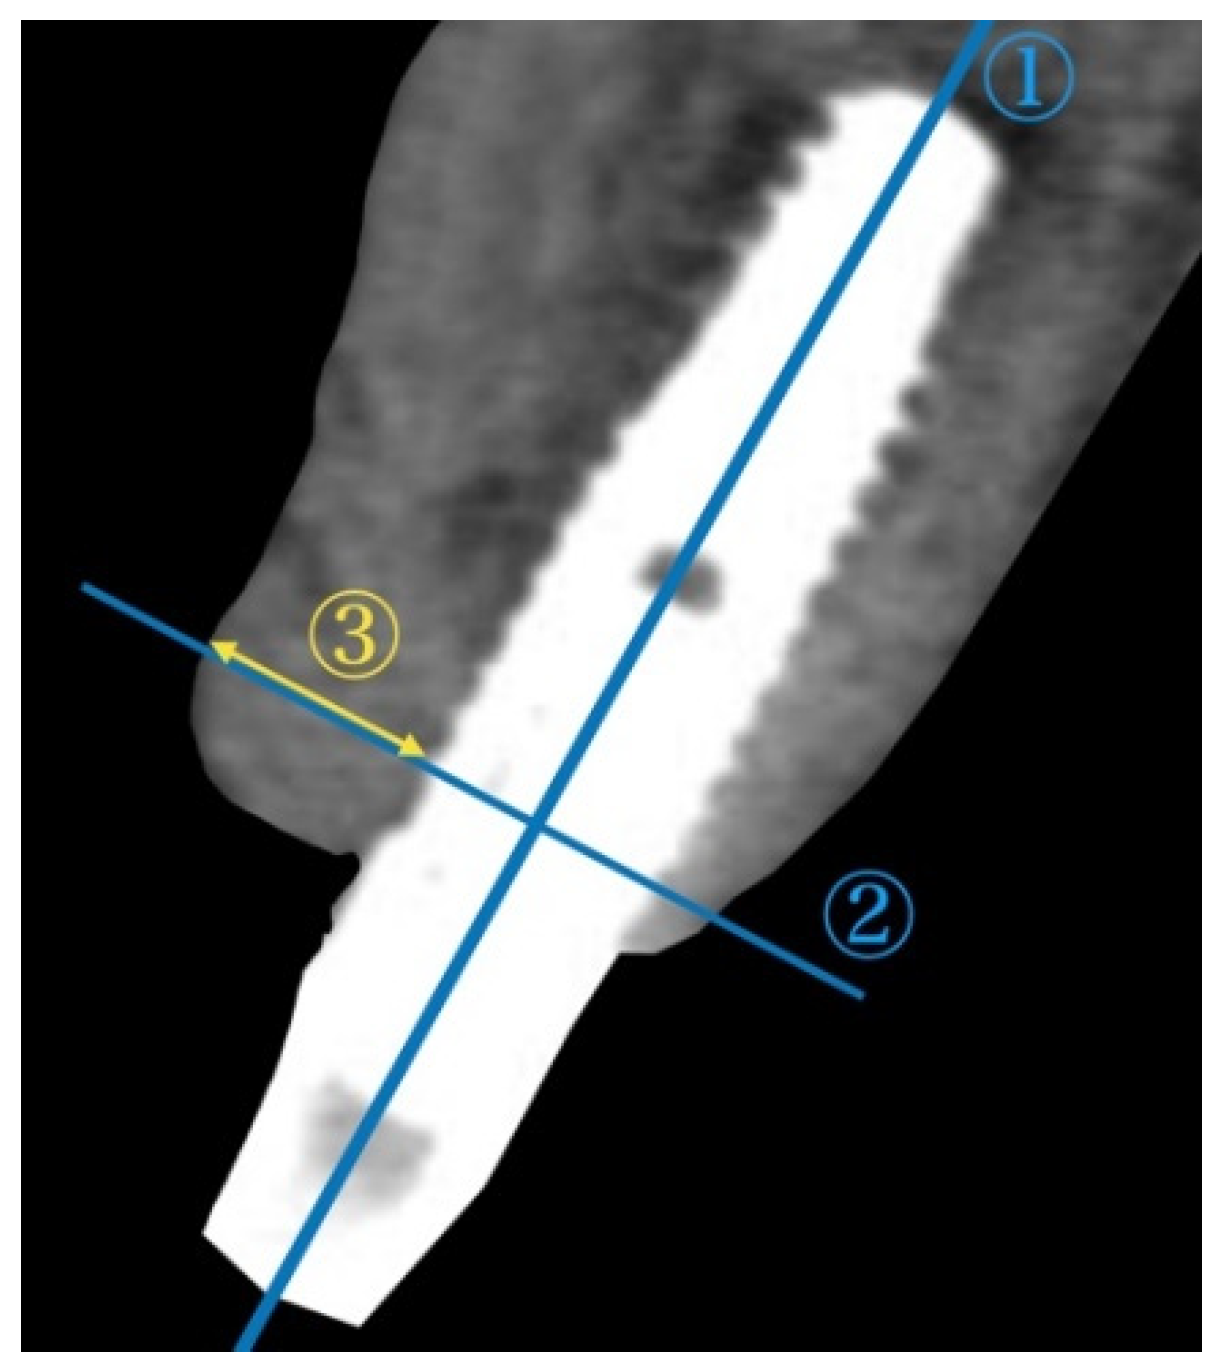

To assess the alterations in the alveolar ridge, CBCT images of the implant sites were acquired immediately after surgery and after permanent restoration using Trophy Pan Pro (Yoshida, Tokyo, Japan). The clinical scanning protocol was fixed to a 10 × 10 cm field of view, a voxel size of 90 μ, 360° rotation, resulting in 17.5 s scanning time, at 90 kVp and 5 mA. A cross-sectional slice according to the long axis of the implant was generated by using actual implant lengths as a reference. Two reference lines were subsequently drawn. The horizontal bone thickness from the implant surface at the first thread to the outermost edge of the buccal bone was measured (Figure 3). The radiological measurements were performed by an independent examiner (C.I.)

Figure 3. Assessment of the horizontal bone thickness with cross-sectional CBCT images. ① A vertical line was drawn in the center of the implant. ② The horizontal reference line was drawn perpendicular to the vertical line crossing the first thread of implant. ③ The horizontal bone thickness from the implant surface at the first thread to the outermost edge of the buccal bone was measured. CBCT: cone-beam computed tomography.